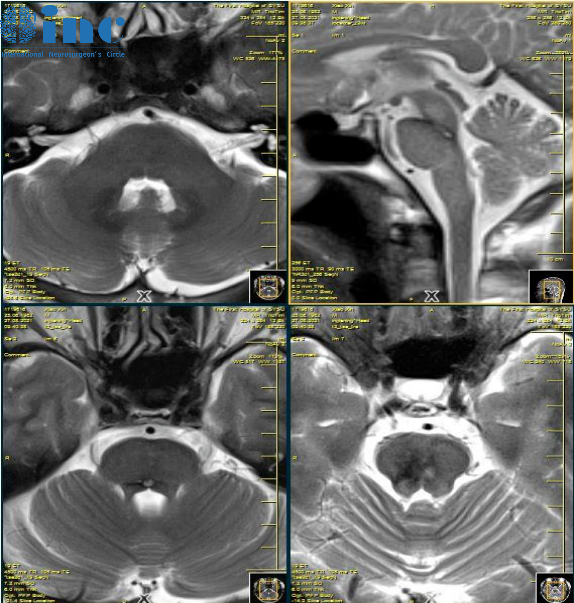

在巴教授手术的300多例脑干海绵状血管瘤患者中,90%以上患者术后获得更好疗效(顺利全切且无任何神经损伤),术后后遗症发生几率和再次出血的几率较低(下图)。术后3天、一周等短期出血的,再次清血肿,预后较好。术后一年等远期出血的需要再次进行手术。

在一次12岁脑干海绵状血管瘤男孩的远程咨询中,患者家长询问道术后孩子预后如何,术后是否会复发?复发概率有多大?

巴教授评估回复

“复发率约为1%。当然,这1%的风险我们需在心里有数,也就是说,在100个海绵状血管瘤的患者之中,99个不会有复发。只有一个患者会复发的,可能在10年以内。所以,我给海绵状血管瘤的病人建议做磁共振复查。先一年一次,后来每两三年一次,只是为了确保万无一失。”

这名患儿选择了巴教授国内示范手术,全切肿瘤恢复正常生活,术后1年没有复发。